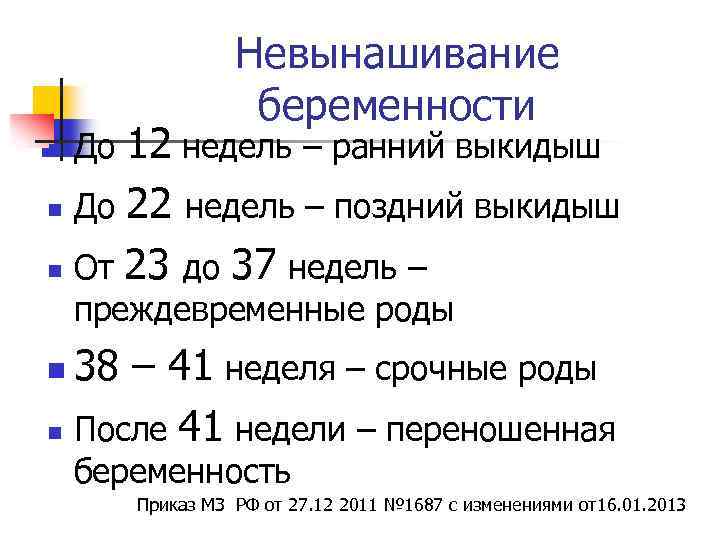

Невынашивание беременности 12 недель – ранний выкидыш n До 22 недель – поздний выкидыш n От 23 до 37 недель – n До преждевременные роды 38 – 41 неделя – срочные роды n После 41 недели – переношенная n беременность Приказ МЗ РФ от 27. 12 2011 № 1687 с изменениями от16. 01. 2013

Критические сроки угрозы прерывания n 2 -3 недели- имплантация; n 4 -12 недель - плацентация; n 18 -22 недель - увеличение объема матки.

Морфологические критерии позднего выкидыша n Масса плода – менее 500 гр n n Длина – менее 25 см Срок беременности менее 22 недель